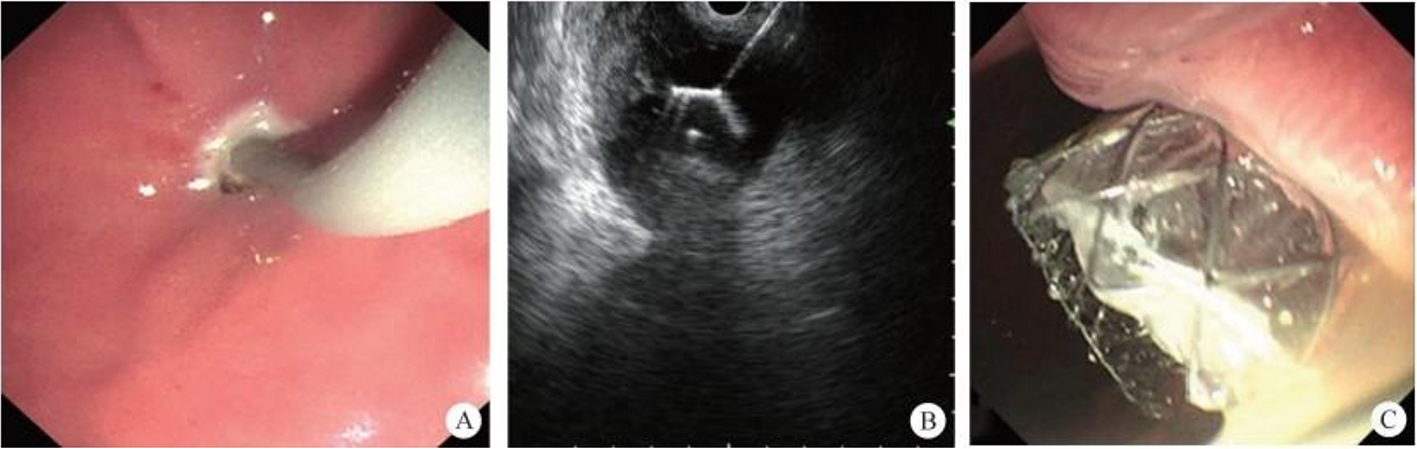

2. Submucosal tunnel endoscopic resection (STER). STER is a new endoscopic technique for the treatment of gastrointestinal muscularis propria tumors; it is an endoscopic surgical modality evolved from POEM, which mainly applies to the excision of gastrointestinal muscularis propria tumors. In sites like the esophagus, gastroesophageal junction, gastric antrum, firstly, one starts by making a small incision in the mucosal surface, then the endoscope goes deeper into it, to create a tunnel in the submucosa, to completely remove the tumor under direct vision, while preserving the integrity of the mucous surface of the digestive tract. After complete resection of the tumor, the opening of the mucosal tunnel was closed with metal clips to avoid perforation of the digestive tract and to reduce postoperative complications such as digestive tract leakage, etc. This method has the advantages of short operation time, less trauma, less pain, low cost, and quick recovery of patients. It can completely dissect the tumor in a single operation, while maintaining the integrity of the digestive tract, and has the same therapeutic effect as classical surgery, and there is no postoperative scar on the surface of the body.